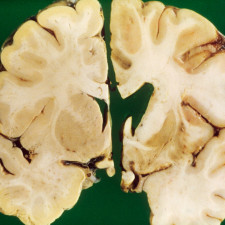

Buňky jsou základní stavební jednotkou všech živých organismů. Hluboko v nich se nacházejí geny, malé úseky DNA, které nesou genetickou informaci a návod pro tělo, jak si vyrábět bílkoviny. Jedná se o bílkoviny, které mají v těle nespočet úkolů – od role stavebních prvků po hlavní regulaci tělesných funkcí.

„Geny nesou základní informace, které dědíme od našich rodičů. V některých situacích může docházet k mutacím, které způsobují vzácná onemocnění. S těmi může nově pomáhat genová a buněčná terapie, která genetické defekty cíleně řeší,“ říká profesor Macek.

Cílem buněčné terapie je obnovit nebo pozměnit určitý soubor buněk v našem těle. Při terapii jsou využívány buňky léčeného pacienta nebo dárce. Terapie s využitím dárcovských buněk jsou již známé například v podobě transplantace kostní dřeně u leukémie.

Při této proceduře ale nejsou buňky od dárce nijak upravené. Nové terapie využívají vlastních buněk pacienta nebo dárce. Ty jsou po odebrání upraveny v laboratoři tak, aby v těle splnily určitou léčebnou funkci, následně jsou vráceny zpět do těla.

Genová terapie léčí onemocnění prostřednictvím genů, a to několika způsoby: přidáním nového genu do buněk pacienta, nahrazením narušených genů nebo zablokováním nežádoucí aktivity určitých genů. „Aby se nové upravené geny dostaly do buněk pacienta, využívají se speciální přenašeče, tzv. vektory. Vektory jsou často viry zbavené vlastní aktivity – nemohou tak vyvolat žádná onemocnění.“

Použity jsou pouze jako schránka, která dopraví nový gen do buněk pacienta. Nový fungující gen uvnitř buněk zajistí, že tělo dokáže správně tvořit bílkoviny potřebné pro vykonávání specifických funkcí.